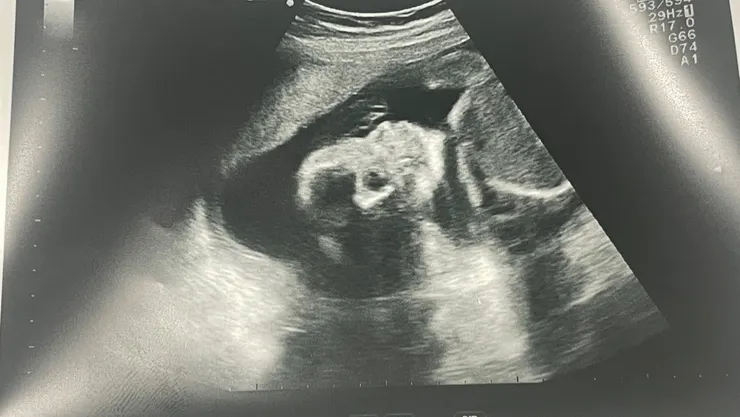

這次24週超音波呈像,寶寶側躺照

看起來是有雙下巴的樣子嗎?:))

24週胎兒超音波影響/Ching拍攝